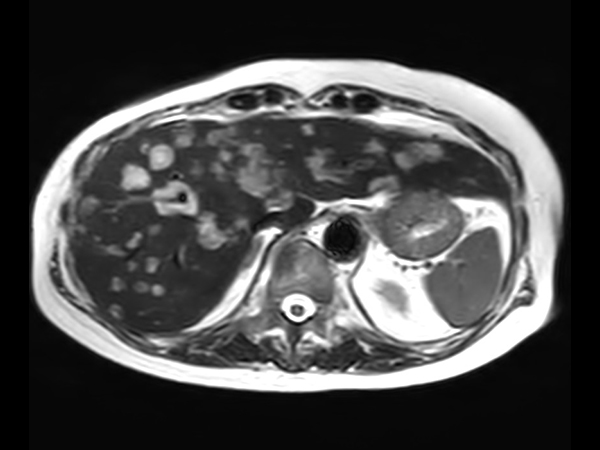

Liver metastasis with SmartSpeed Precise

Axial T2w SSh

Axial Heavy T2w SSh FatSat